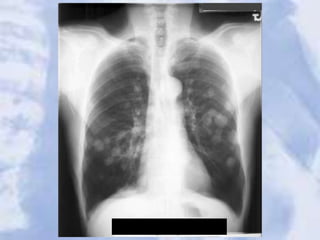

Metastatic Lung Cancer: multiple nodules seen

Metastatic Lung Cancer:multiple nodules seen